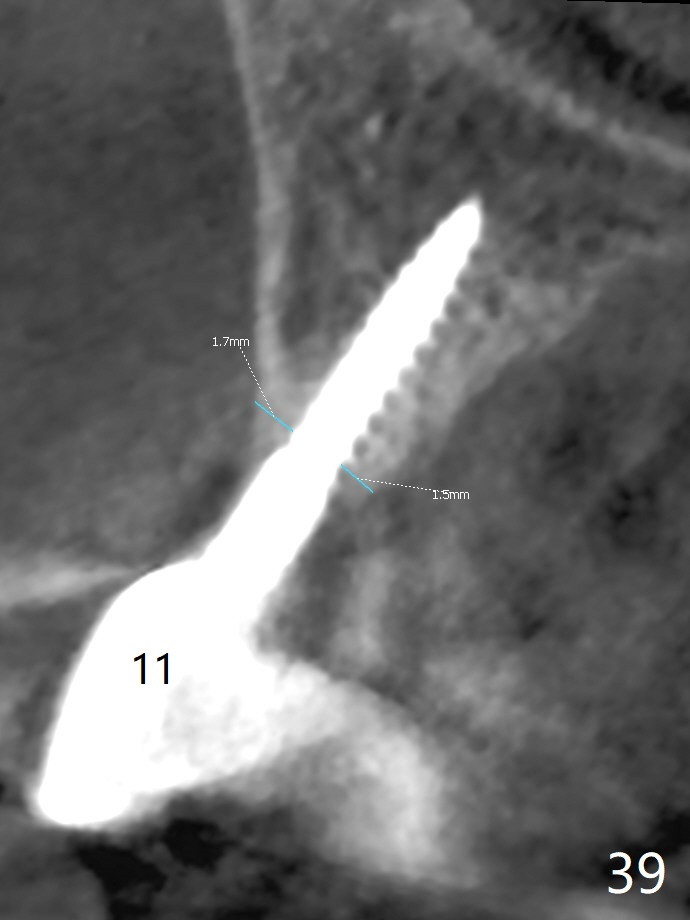

CT is taken 2 years 2 months postop (Fig.35-41).  All of the implants except #10 are placed in the middle of the alveolus.